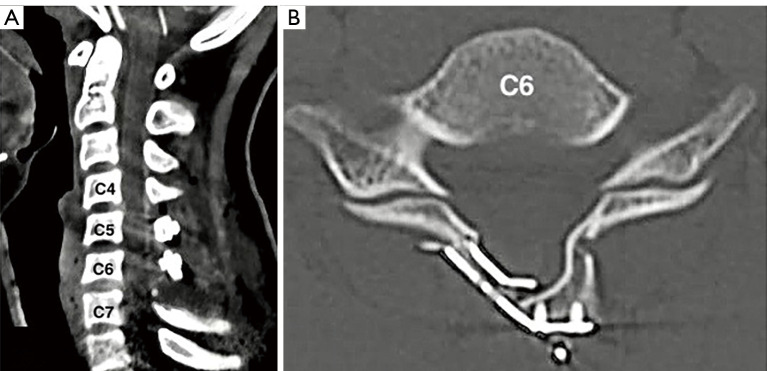

背景:自发性脊髓硬膜外血肿(SSEH)是脊髓硬膜外腔内的血肿,其根本原因不是外伤或先天性的,被认为是一种非常罕见的儿童神经外科急诊疾病,可导致脊髓压迫和神经功能障碍。本文就儿童 SSEH 的具体特征、临床表现和处理策略为临床医生提供有用的信息和指导,以获得更好的治疗效果:一名 14 岁男孩因颈部疼痛急性发作并向右肩放射,同时伴有进行性右侧偏瘫。颈椎磁共振成像(MRI)显示,C4-C7 处存在右侧后外侧急性脊髓硬膜外血肿。患者接受了紧急开门椎板成形术(C5-C6)和部分椎板切除术(C4 和 C7),并完全清除了血肿。术后患者完全康复,无神经功能障碍。我们在 PubMed 电子数据库中进行了文献检索,以找出 2000 年 1 月至 2023 年 12 月期间发表的以儿童 SSEH 为主题的英文文章。我们找到了81篇文章,共95例儿童SSEH病例,提供了性别、年龄、临床表现、病因、血肿位置、治疗方式和结果等方面的对比数据:儿童 SSEH 是一种非常罕见的神经外科急诊疾病。及时、正确的检查对确诊和早期手术减压至关重要。适当的手术减压可降低硬膜内压,增加脊髓的血液灌注,从而最终减少缺血,防止继发性脊髓损伤。因此,患者有望完全康复。

Case description: A 14-year-old boy presented with an acute onset of neck pain radiating to the right shoulder and progressive right hemiparesis. The cervical spine magnetic resonance imaging (MRI) revealed a right posterolateral hyperacute spinal epidural hematoma at C4-C7. The patient underwent an emergent open-door laminoplasty (C5-C6) with partial laminectomy (C4 and C7) and complete evacuation of the hematoma. The patient had a complete recovery after surgery with no neurological deficits. A literature search in the PubMed electronic database was performed to identify published English articles between January 2000 to December 2023 focusing on SSEH in children. We have found 81 articles with a total of 95 cases of SSEH in children, providing comparison data on sex, age, clinical presentation, etiology, location of the hematoma, treatment modalities, and outcomes.